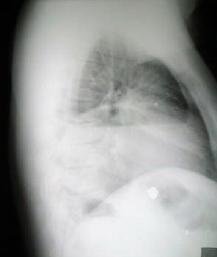

Rx. tórax (hace 6 meses), posterior al egreso de su antecedente traumatico.

Rx. Tórax al momento de su Ingreso. motivo de su referencia a nuestro hospital.